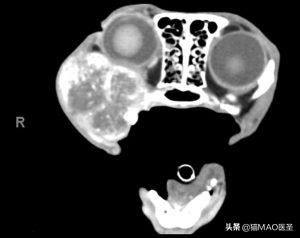

CT可以提供更多信息,因为它可以显示疾病的程度,用于治疗计划(手术或放射治疗)(图7)。建议在CT检查中包括胸部,以评估可能的肺转移性疾病。

计算机断层扫描的猫与增殖性右上颌肿块,组织学证实为猫口腔鳞状细胞癌。